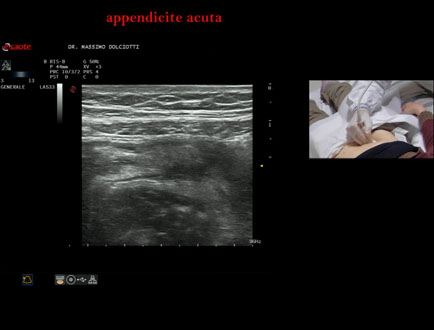

Data inserimento: 21/01/2025

Ecografia del: 16/01/2025

Strumento: Esaote MyLab Eight

Sonda: Convex Multifrequenza 1-8 MHz e Lineare Multifrequenza 4-15 MHz

Età Paziente: M 45 anni

Motivazione dell'esame: da 2 giorni dolore in sede ileo-cecale

Commento all'esame: le immagini ed il video documentano in sede ileo-cecale, il verme appendicolare di spessore aumentato pari a 7,6 / 8,1 mm ( v.n. < 6 mm), da ricondurre ad appendicite acuta.

Conclusioni: appendicite acuta (acute appendicitis).

Presentazione: Dr. Massimo Dolciotti - Ancona

Elaborazione digitale: Andrea Dini - Ancona